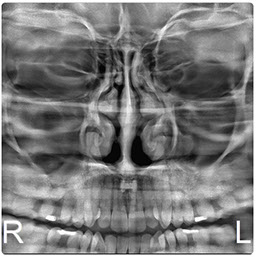

Radiografía de senos Paranasales

Telerradiografía Antero Posterior

El Eagle 2D Pan/Tele ofrece todos los exámenes en el perfil panorámico (panorámica estándar, senos maxilares, baja dosis, bitewing, ATM, ortogonalidad perfeccionada, panorámica infantil y bitewing ortogonalidad perfeccionada) y todos los exámenes en el perfil cefalométrico (Posteroanterior, Antero-posterior, 45 Grados, Lateral, Carpal, PA de Walters, Axial Bazal, Hirtz).